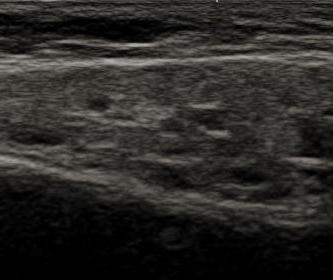

おたふく風邪との鑑別が難しい時などは、当院では超音波検査を行っています。反復性耳下腺炎では、耳下腺組織の中に小円形低エコー域の多発が見られます。この所見は、拡張した導管かその周囲のリンパ球浸潤によるものだと言われています。

図は腫れがほとんどなく、原因不明の耳下部の痛みだけを何回も繰り返して、多くの病院を受診しても診断がつかず、当院を受診した子の超音波検査所見です。グレーの耳下腺組織の中に多数の黒い丸が見られます。この子は、超音波検査をしなければ、診断がつかなかったでしょう。